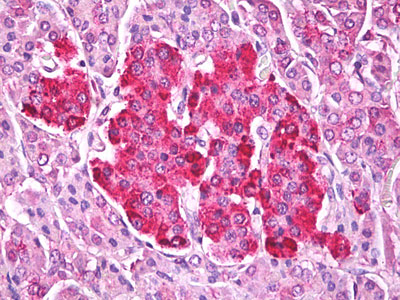

Anti-TTR / Transthyretin antibody IHC of human pancreas, islets of Langerhans. |